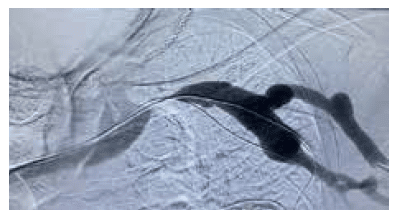

An 85-year-old male patient on haemodialysis for 15 years with swollen left arm and reduced AV circuit competence. The image below shows a clinically significant subclavian stenosis.